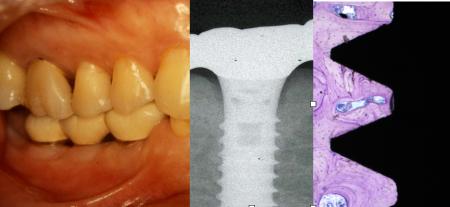

インプラントのオッセオインテグレーション

しかし、インプラントを治療に入れていない診療室に、他院でインプラントを入れた患者さんが来た

場合に、そのメインテナンスの方法、予後の診査方法を知らないで、患者さんの口腔管理はできない

時代になっています。